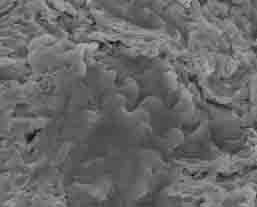

- fundamental researches, for example focused on the cell behavior in contact with different titanium surfaces, and the influence of roughness and chemical modification on bone implant contact;